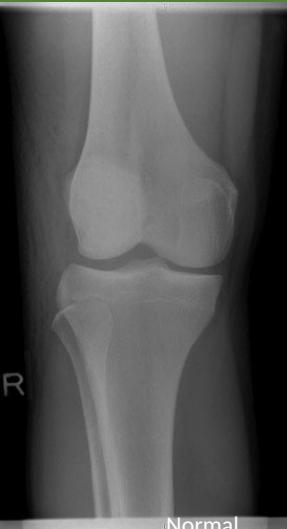

Imaging Studies

- Standard Radiographs:

- Both knees AP standing views (weight-bearing)

- Lateral views of both knees

- Skyline view (patellofemoral assessment)